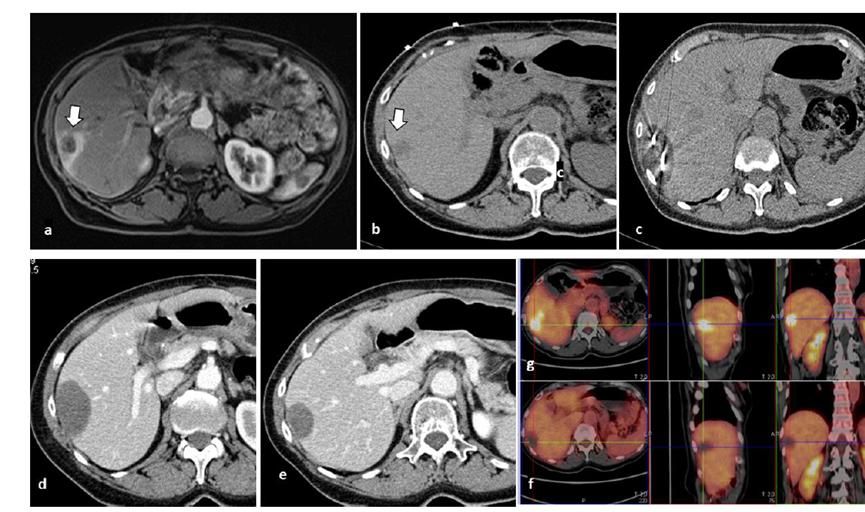

79 岁男性,肝转移(结直肠癌)肿瘤的完全消融病例

( a ) 轴向 MRI 和 ( b ) 轴向 CT 显示肝S8段有一个16mm的病灶,邻近肝缘。( c )冷冻消融期间CT显示放置了2个冷冻探针,低密度冰球包围病灶。(d)术后1个月随访 CT显示冰球对应的坏死区域,未见复发。(f)与基线影像(g)相比,12个月后的FDG-PET/CT显示未见FDG摄取。

(a)轴向CT显示病变位置毗邻心脏和上腔静脉(黑色箭头)。1个月后的轴向(e)和冠状位(f)增强CT扫描显示低密度区域,由于肉芽组织反应引起的边缘增强。